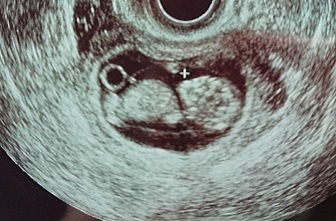

10週4日(10w4d・女の子)|かんかんりんりん さん(34歳)

エコー写真撮影時のエピソード:

妊娠がわかっても生理が来ないという事だけで全く実感がない状態でしたが、このちょっとだけ人間っぽいエコー写真をみて初めて赤ちゃんがいるんだな…と感じた1枚です。パパをこれを見て初めてかわいい…クリオネ見たい。とお腹の赤ちゃんに興味を持ってくれました。